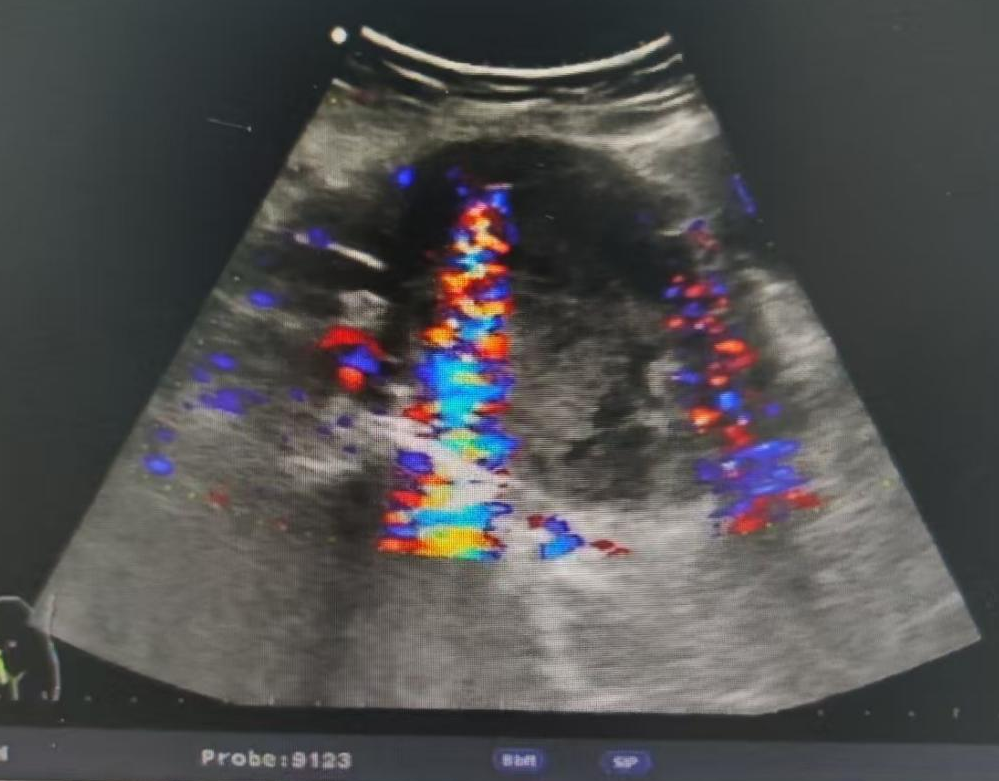

腹部探头

阿洛卡

UST-9123

彩色血流成像有干扰。如下图